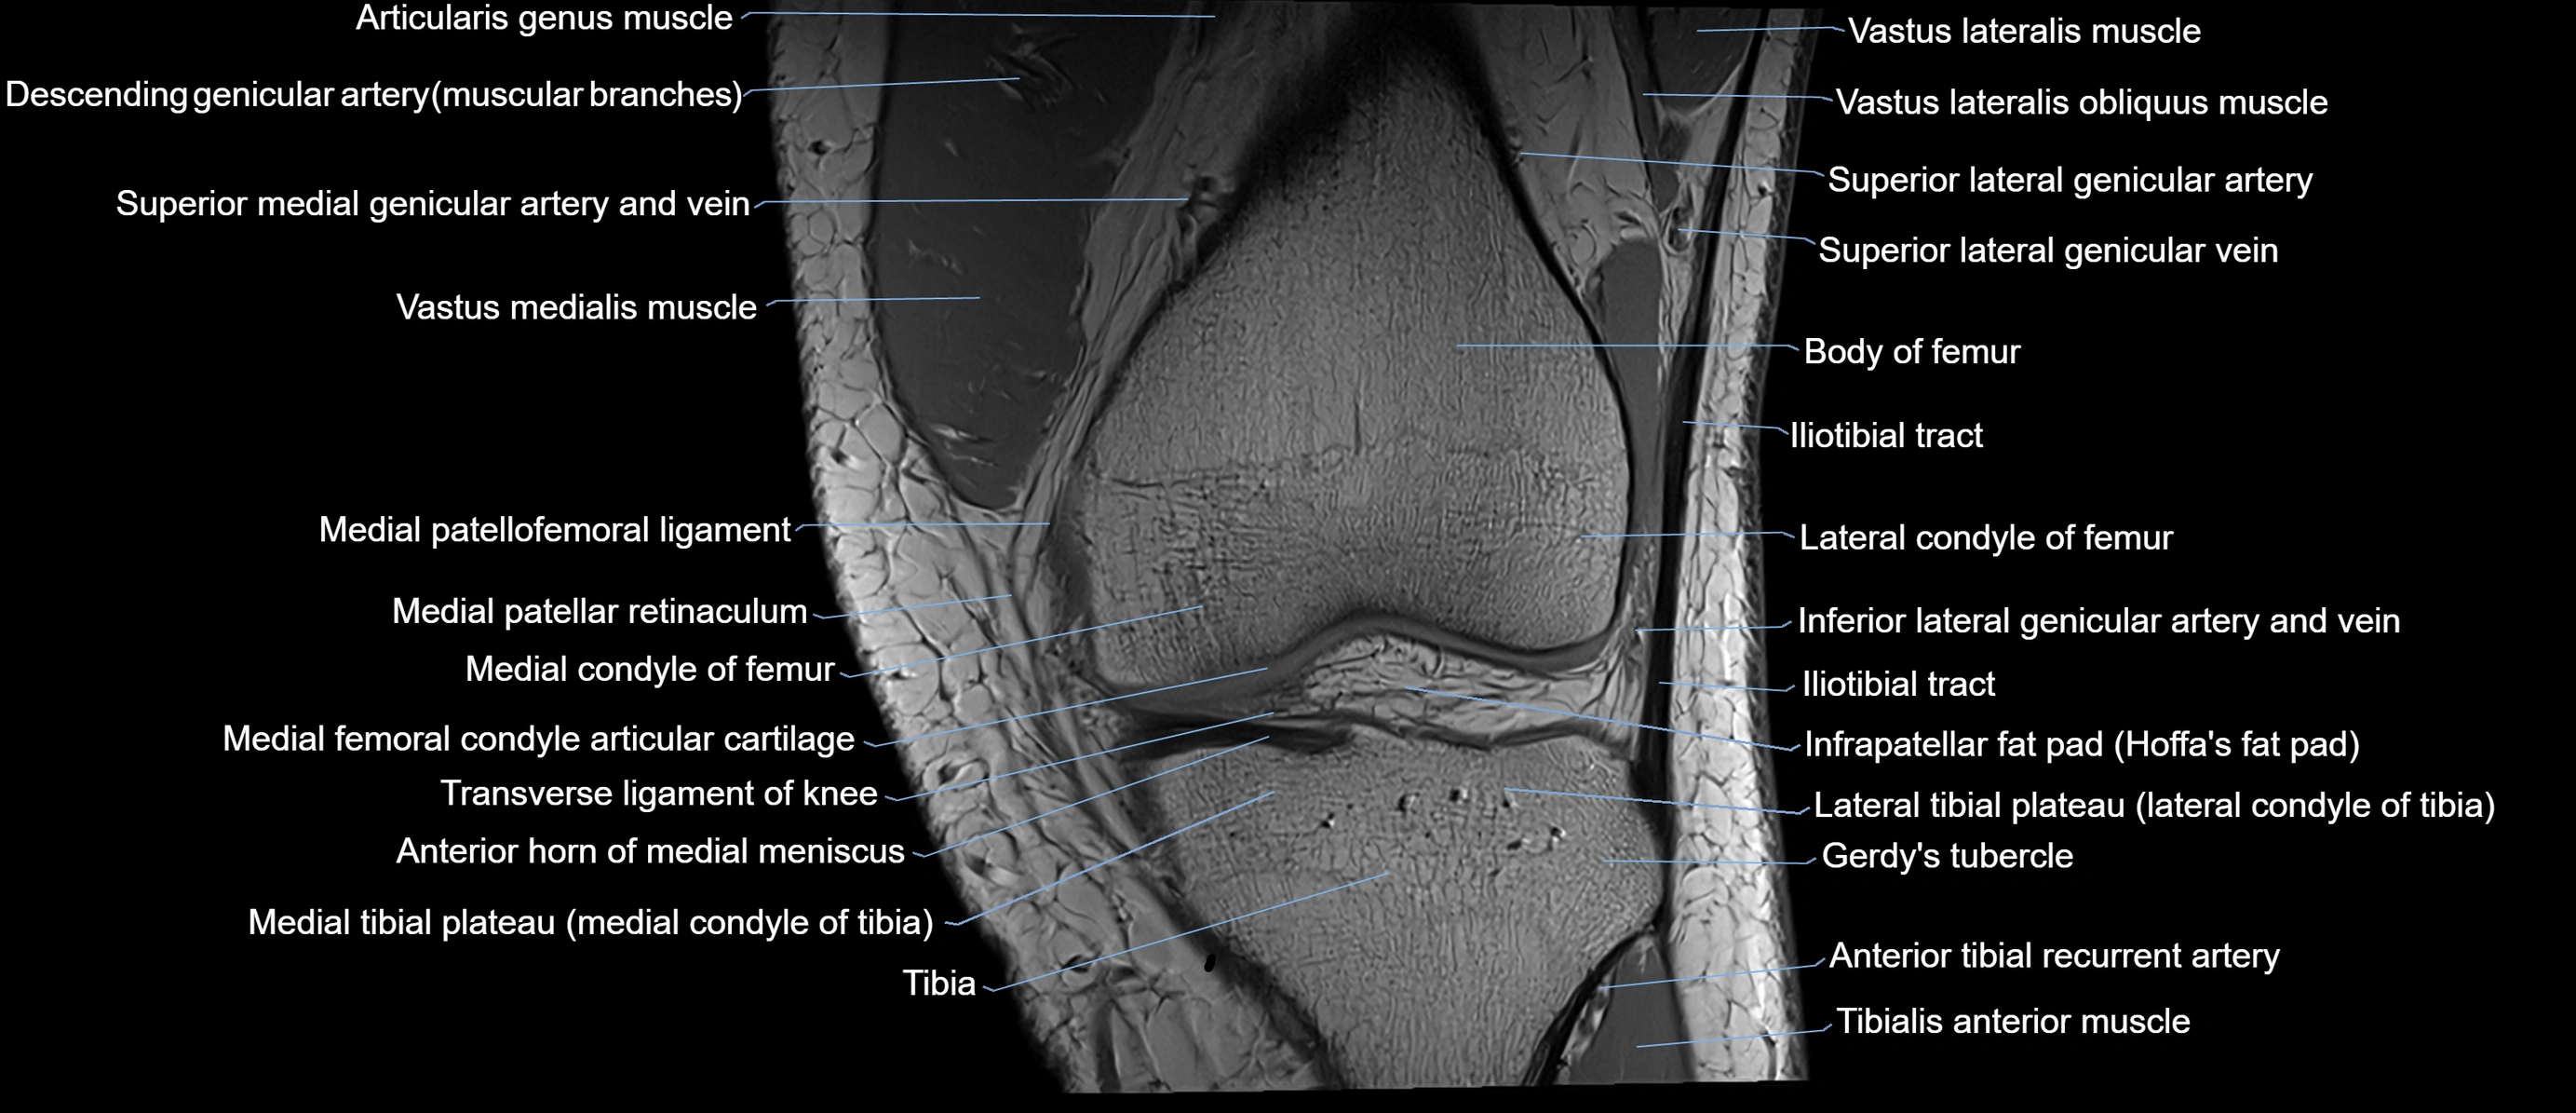

- Anterior horn of medial meniscus

- Gerdy’s tubercle

- Lateral condyle of femur

- Lateral tibial plateau

- Medial condyle of femur

- Medial condyle of tibia

- Medial patellar retinaculum

- Medial patellofemoral ligament

- Medial tibial plateau

- Patellar tendon (patellar ligament)

- Superior lateral genicular artery

- Superior lateral genicular vein

- Tibia

- Tibialis anterior muscle

- Transverse ligament of knee